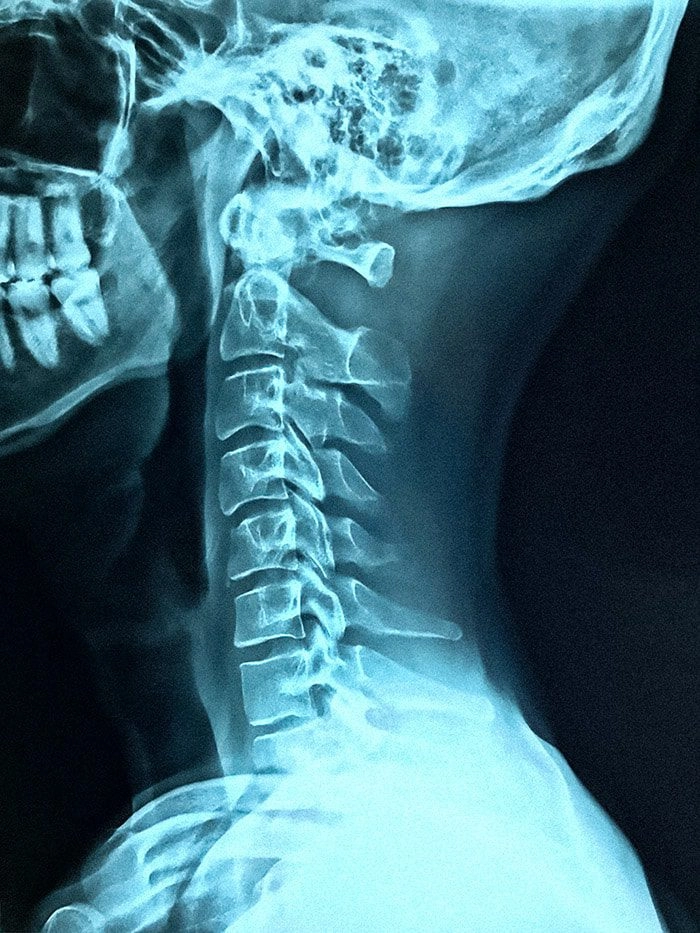

This is where chiropractic care and weightlifting come into play. Since all muscles connect to either the joints or the spine, it only makes sense that the joints and spine need to be in proper alignment for the muscles to work in balance with one another.

When your spine is not aligned, the muscles on one side of the body will be forced to work harder than the other side. This is a sure set-up for injury or injuries to occur.

Weight lifting makes the body stronger, but it also puts extra stress on the bones, muscles, and joints, causing them to adapt. This extra strain, however, can also misalign the spine and pinch the nerves.

Pinched nerves mean lower levels of muscle strength and the formation of scar tissue. You might not even be aware of this as this condition is not always painful.

Chiropractic care for weightlifters involves making adjustments so that the spine is put back into its natural, proper position. This allows the muscles to reach their maximum potential. Taking protein supplements/powders from trusted manufacturers can also help your muscles reach their max potential.

Your muscles function and perform based on information sent and received via the central nervous system. Similar to a landline phone, information is sent and received from the brain to the muscles and back again via the central nervous system, which runs through the spinal column.

When the joints in the spine are out of place or are not moving correctly, information cannot be sent properly. This can make you feel as if everything is OK when it isn’t or the opposite; that something hurts here when the pain is located elsewhere.

Chiropractic care for weightlifters can restore function to joints, align the spine and improve range of motion. This opens up communication once more and allows the body to do more healing on its own.